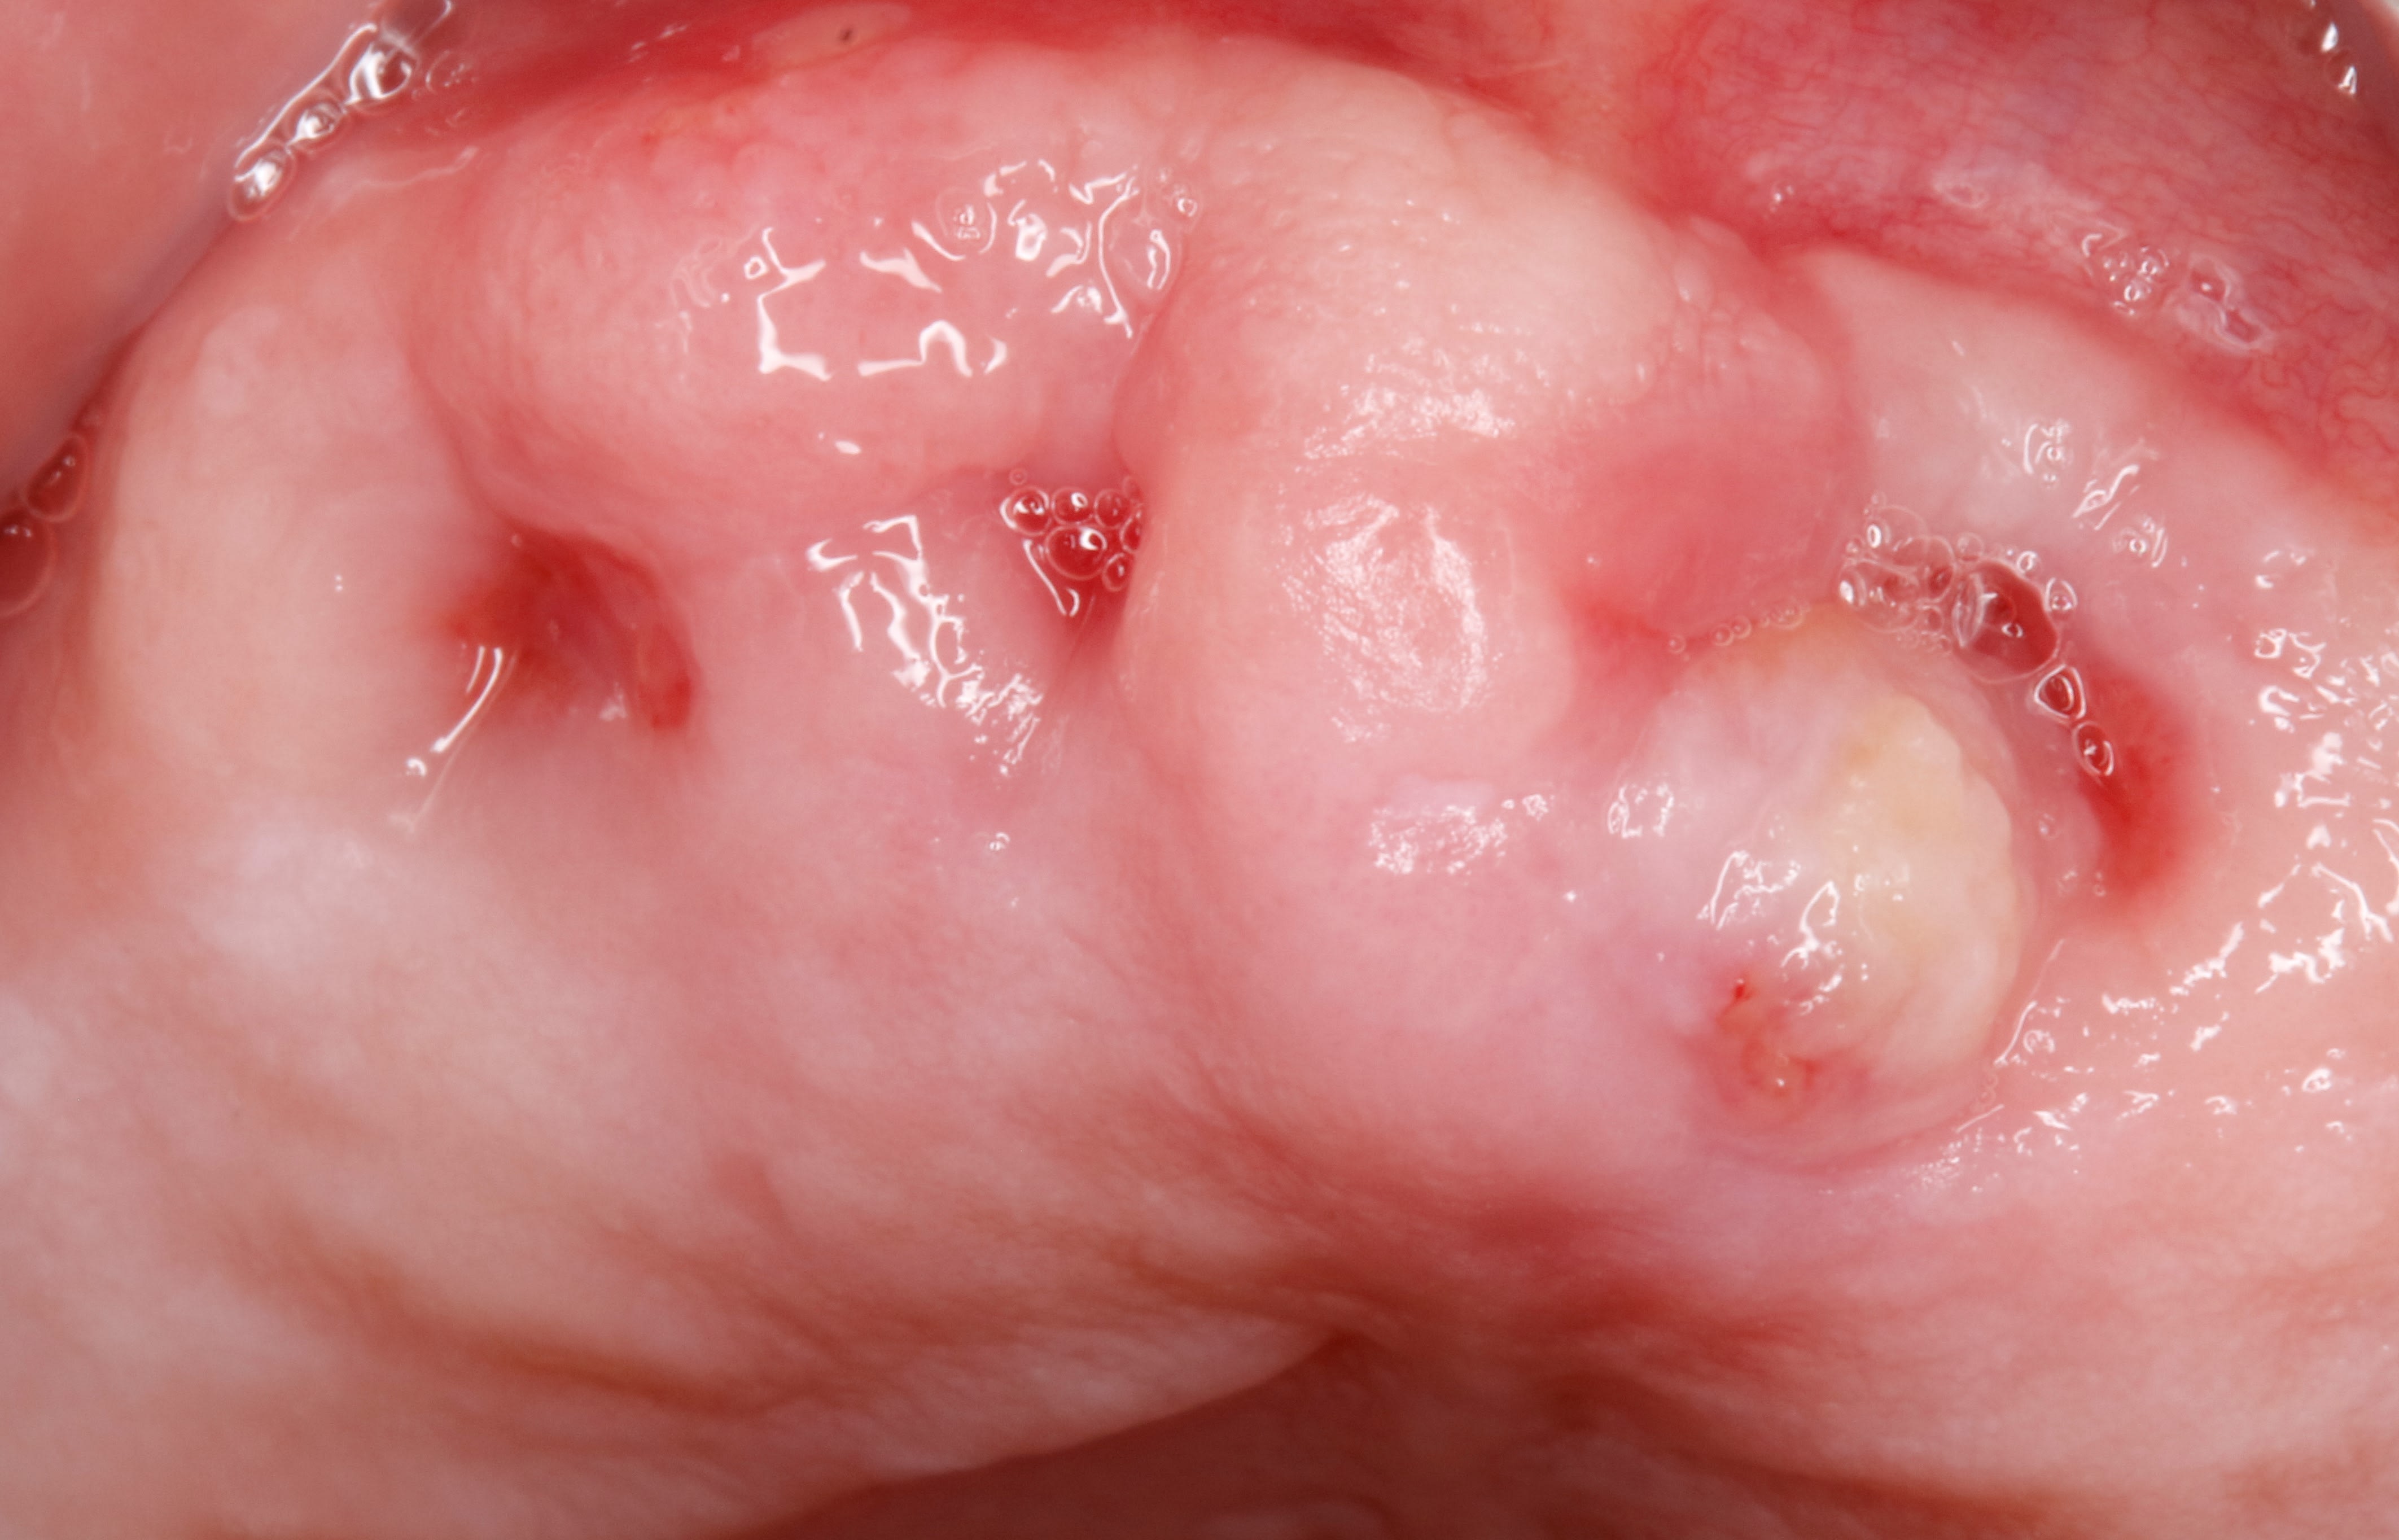

Patient 45 ans non fumeur, bonne hygiène.

27 présentait un abcès fistulé, je prescrit Amox 2g et je le revoit 6 jours après pour extraction, le kyste est important et il y a une CBS. Je referme avec gelatemp et sutures plus conseils pour la cbs.

Une semaine après le patient revient, il a mal type sinusite, il y a un écoulement purulent et une sorte de granulome qui a poussé dans l’alvéole. Je fais un curetage et 10 jours d’augmentin. Je le revois 2 semaine plus tard, même topo. Il y a à nouveau un granulome et un écoulement purulent.

La photo date d’il y a 2 semaines, mais aujourd’hui, c’est pareil. Je ne sait pas trop quoi faire. Attendre, ORL, ...?

Ça ne ressemble pas à de la neo gencive c’est vraiment granulomateux. Pas d’air qui passe en Valsalva.

Denteo , c est le genre de tissus qu on a pas l habitude se voir , pourtant on en a enlevé des dents . c est comme un tissus de cicatrisation mais plus globuleux.

entre la fraise et et la framboise .

C'est exactement ca, comme des petites groseilles molles, avec du pus...

J’ai pas souvent mais de temps en temps ce type de lésion, une sorte de masse molle avec des effets tachetés , tu appuies, ça se perce et du pue s’en écoule. je place sous antibio type bi rodogyl et ça régresse spontanément autour de 2 semaines . si ça persiste, pas joli, il faut,évidemment, envoyer à un stomato. Pour moi pas le feu au lac. Par contre avec une CBS, je calmerai au niveau des curetages.

Pareil, j'attendais même si ça semble long. Ça m'arrive de temps en temps ce genre d'epulis degueu ... mais en général va revient propre au bout d'un moment. Notamment sur des vieilles racines sous gencive, avec cet aspect de framboise, et bin même après avoir giclé la racine, et cureté tout ce tissus inflammatoire, ça revient.